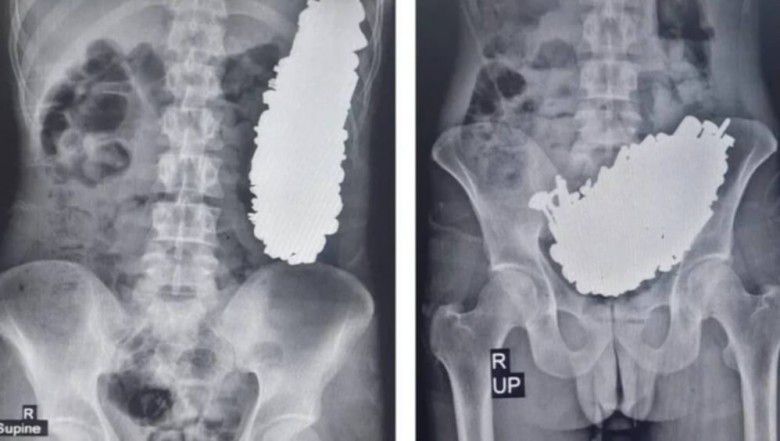

Pasien kemudian melakukan tindakan X-ray untuk melihat kondisi tubuhnya. Dan betapa terkejutnya, dokter menemukan adanya 452 benda logam yang bersarang di perut pria tersebut. Ada kunci, baut, mur hingga sekrup.

"Pasien memiliki indeks massa tubuh (IMT) 19,5 kg/m 2. Rontgen abdomen pasien menunjukkan banyak benda logam di lambungnya. Selama endoskopi, banyak benda asing ditemukan di antrum lambung, yang menyebabkan obstruksi saluran keluar lambung," demikian keterangan dari jurnal tersebut, dikutip Selasa (20/8/2024).

:quality(80):format(jpeg)/entries/2024-08/25/57235-1-a194f69935270a524513263c89b72846.jpg) Hasil rontgen pria yang memakan benda logam (via Journal of Medical Case Report)

Hasil rontgen pria yang memakan benda logam (via Journal of Medical Case Report)